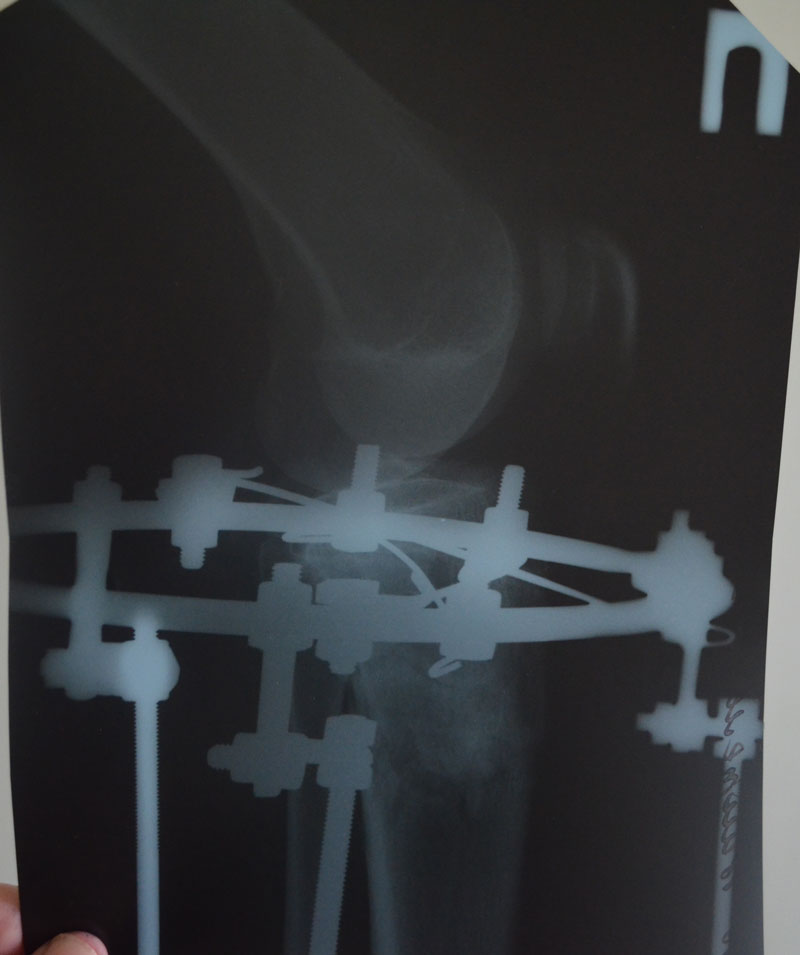

- Диагноз: О-образная деформация нижних конечностей

Всё хорошо, ножки ровные, продолжаем фиксацию!

По рентгену, ось ровнейшая. Правая срослась, а левая... Ходить Вам ещё минимум 3 недели, после делайте ещё рентген и отправляйте по эл. почте. Начинайте принимать препараты кальция и мумиё - его нужно принимать так: развести в 0,5 л. банке 10 таблеток - мумиё, до полного растворения таблеток. После этого, принимать по 1 ст. ложки раствора 3 раза в день. Хранить в холодильнике.